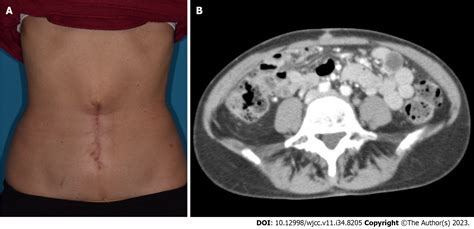

The human body often communicates the presence of underlying systemic disease through subtle, external indicators that can easily be overlooked. Among these clinical signs, the Sister Mary Joseph Nodule stands out as a rare but highly significant physical manifestation. Named after a surgical assistant to Dr. William Mayo, this clinical sign typically presents as a palpable, firm nodule located at the umbilicus. It serves as a stark warning sign, often indicating an advanced, metastatic malignancy originating from within the abdominal or pelvic cavities. Recognizing this nodule early is crucial, as it often alters the trajectory of patient care and diagnostic urgency.

The Sister Mary Joseph Nodule is not a primary skin condition but rather a secondary metastasis. Patients typically present with a painless or occasionally tender umbilical mass that has developed over weeks or months. Because the umbilicus is a relatively non-distinctive area of the body, patients may initially mistake these lumps for common benign conditions such as hernias or granulomas. However, clinical characteristics that raise suspicion include:

• Hard, irregular texture: Unlike soft umbilical hernias, these nodules are typically firm or fixed.

• Discoloration: The overlying skin may appear erythematous, violaceous, or even ulcerated as the mass grows.

• Imaging Studies: A Contrast-enhanced CT scan of the abdomen and pelvis is the gold standard for identifying the primary tumor site and assessing the extent of metastatic disease.

• Biopsy: Fine-needle aspiration (FNA) or an excisional biopsy of the umbilical nodule is essential for histological confirmation and immunohistochemical analysis.